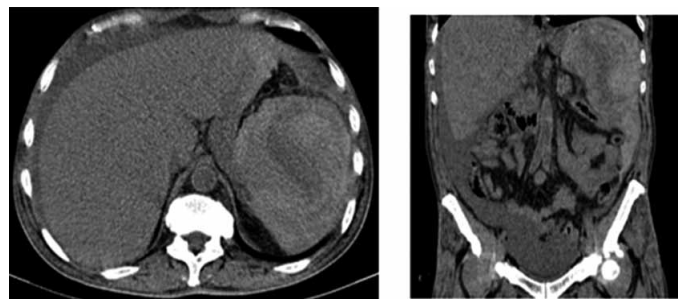

A tomografia computadorizada de abdome está demonstrada a seguir:

(Coimbra, B. M.; Cardoso. T. T. Brad Cases - Brazilian Radiological Cases 2022, 1(4): 474-480)